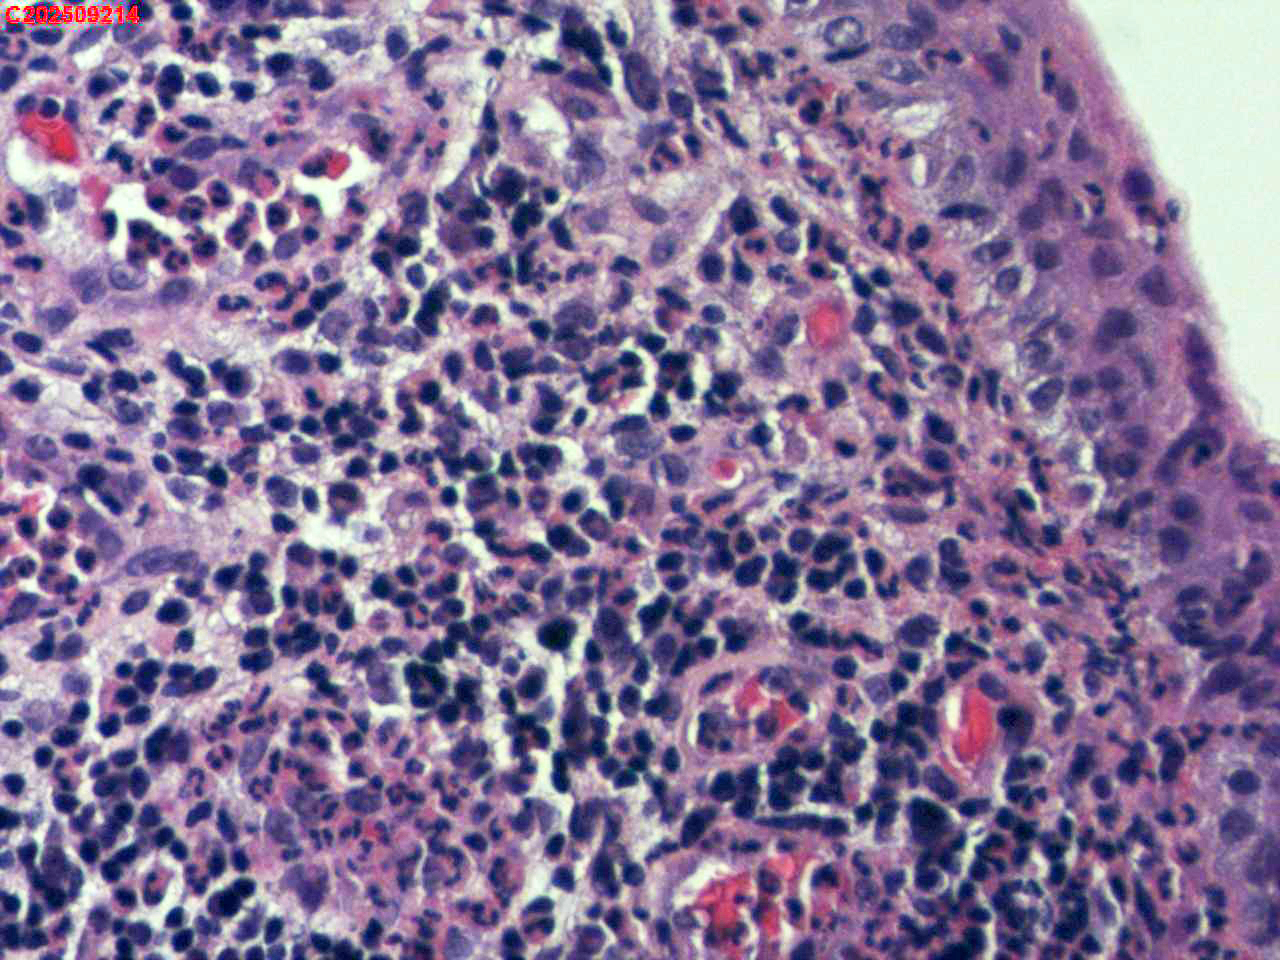

左肺下叶背段咬检组织

性别年龄59岁临床诊断肺结核?肺部感染?

一般病史胸部(平扫):两侧胸廓对称,气管及纵隔居中。双肺纹理增多、紊乱,胸膜下区见多发索条影;双肺见多发大小不等斑片状高密度影,部分呈树芽征样磨玻璃样改变,部分病灶内见支气管含气、少许钙质沉积。气管及大支气管通畅。心脏大小形态可;冠状动脉走行处见多发条形高密度影。双侧胸膜局部肥厚粘连。纵隔内见多发淋巴结影,4L区较大者约10mm* 16mm。

标本名称左肺下叶背段咬检组织

大体所见纤支镜检查:左肺主支气管上叶、下叶及各段级支气管通畅,粘膜无充血,背段外亚段远端可见疑似白色痰栓,灌洗支气管刷检并镜下尝试活检钳清理,发现其质硬考虑为新生物并咬检,该部位深远,且咳嗽及呼吸干扰取材不理想。

毛霉菌病